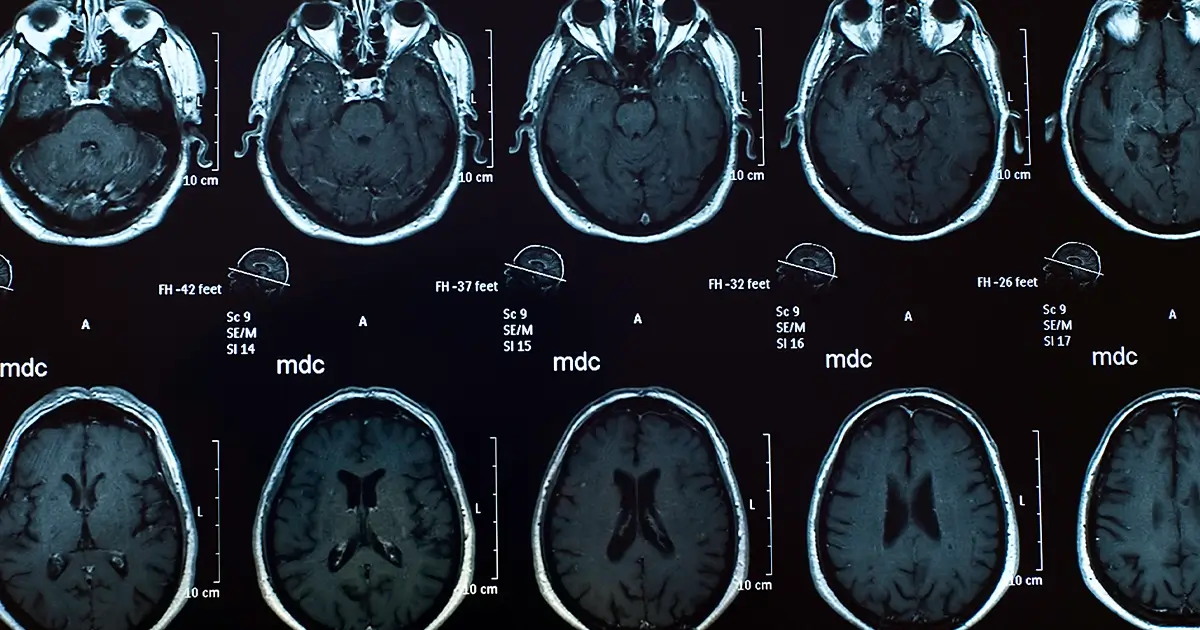

In Fort Lauderdale, the bustling city streets hold a hidden danger that many may not consider—traumatic brain injuries (TBIs). A TBI occurs when there is a forceful bump, blow, or jolt to the head or body, or when an object penetrates the skull and enters the brain. These injuries can have life-altering consequences, ranging from temporary disruptions in brain function to severe, permanent disabilities, or even fatalities.

Unlike visible injuries, TBIs can lurk beneath the surface, initially showing no clear symptoms. The rush of adrenaline or heightened emotions post-accident may mask signs of a TBI, leading victims to believe they’re unharmed. Seeking immediate medical treatment is vital, as it can uncover hidden injuries and provide an accurate diagnosis.